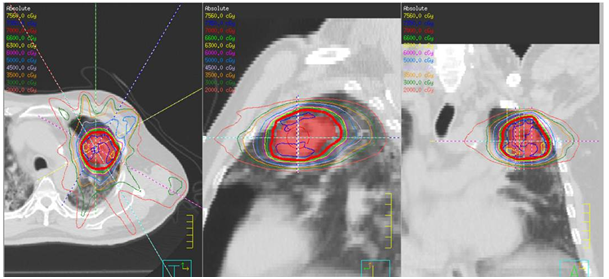

A 72year-old male patient visited the outpatient’s clinic complaining of progressive shortness of his breath. A suspicious opacity was detected on his chest X-ray and contrast- enhanced computed tomography of the chest revealed a 3.0x4.0x3.5 cm mass in the upper left lung. The tomography also identified subplevral honeycombing, traction bronchiectasis and reticular opacities. His clinical and radiologic findings were consistent with IPF. There was no endobroncheal lesion indicated in the fiberoptic bronchoscopy. Transthoracic fine-needle aspiration biopsy confirmed squamous cell lung cancer. For further staging, 18 F-2-fluoro-2-deoxy-d-glucose positron emission tomography and computed tomography (FDG PET/CT) was completed. Metabolic findings were consistent with the known primary tumor without any nodal or metastatic disease. The disease was classified as T2aN0M0 non-small cell lung cancer according to 8th edition of the UICC/AJCC TNM staging system. He also had a history of larynx cancer and vocal cord radiotherapy, chronic obstructive lung disease and arthritis. Due to his complex past medical history and poor performance status, the patient was regarded as medically inoperable. He was also not a good candidate for chemotherapy. Therefore, only definitive radiotherapy was recommended by the multidisciplinary oncology team. Increased risk of the potential side effects depending on radiation treatment especially in the presence of underlying lung disease was explained to the patient comprehensively, and his written informed consent was taken. Radiotherapy dose planning was based on contrast-enhanced 4D-CT (respiratory data sets are ‘binned’ by phase:0-100 % at 10% interval) images fused with FDG-PET/CT. Respiratory corralated imaging (3mm slice thickness) was generated by AcQSim CT simulation of Philips Brillance Big Bore CT, planning was performed by Pinnacle radiation therapy planning system. PTV was integrated tumor volume plus 5 mm. Lung parenchyme was delineated at 50% phase in order to consider the lowest healty lung volume. The prescribed dose was 70 Gy in ten fractions. Treatment plan was generated with six fields (330, 0, 30, 60, 120, 150 gantry degrees) and step and shoot tecnique with 100 segmentations. Mean lung dose was 4,5 Gy and V5, V10, V20 for total lung were 15% , 10% and 9% respectively. For ipsilateral lung, V20= 19%, V10= 22% V5=25% and mean dose was 9,6 Gy. Mean heart dose was 0.3 Gy, maximum dose was 0,8 Gy and also V40 was 0. One fourth of esophagus was within the treatment volume and V50, maximum dose and mean dose were 0, 13 Gy and 2,3 Gy, respectively. The patient completed the radiotherapy at Trilogy (Varian Medical Systems, United States) without any complications (Figure 1).

Figure 1 A) SABR treatment fields in 3 dimensions defining the left side treatment fields.

B) Axial, sagittal, coronal slides of treatment field of SABR treatment.